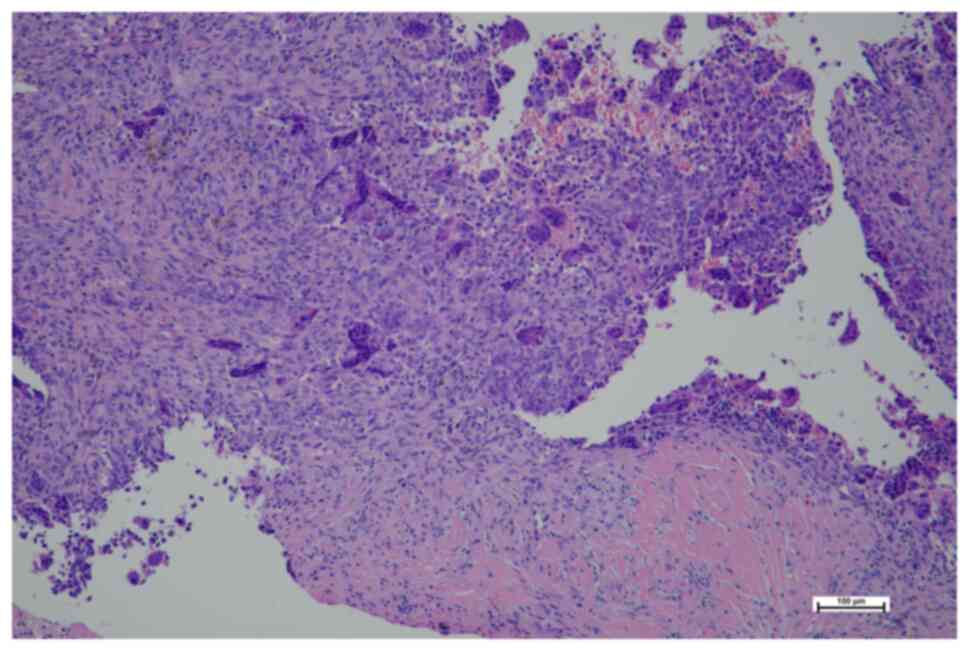

In January 2019, an 11-year-old female was referred to the Masaryk Memorial Cancer Institute Sarcoma Center with a 2-month history of pain in the right foot. MRI scans showed a 3 cm thickening of the bone in the V. metatarsal diaphysis (Fig. 11). The histopathology report showed an intermediate-grade periosteal osteosarcoma (Fig. 12). The patient had no lymph node involvement or metastases. The Musculoskeletal Tumor Committee recommended en bloc resection with bone allograft reconstruction using a plate. The final histopathology report confirmed the initial findings from the biopsy (Fig. 13). After 2 years, a follow-up plain radiographs showed ossification on the allograft surface (Fig. 14), leading to a biopsy to check for any signs of local recurrence. The biopsy results showed no evidence of malignancy (Fig. 15). At the time of writing, the patient completed 5 years of follow-up appointments with no signs of disease recurrence.

Case 3. Hematoxylin and eosin staining following open biopsy. Magnification, ×100. Histological section showing well-differentiated bone trabeculae, surrounded by atypical osteoblasts with low-to-intermediate grade atypia.

Case 3. Hematoxylin and eosin staining following resection. Magnification, ×100. The surface of the tumor displayed trabeculae of mature bone surrounded by atypical osteoblasts. These trabeculae were connected to a mass of atypical cartilaginous matrix, with atypia ranging from low to intermediate grade.